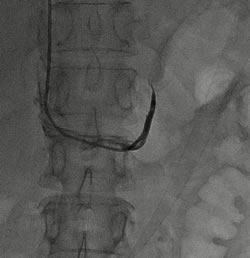

左侧肾上腺静脉插管采血 右侧肾上腺静脉插管采血